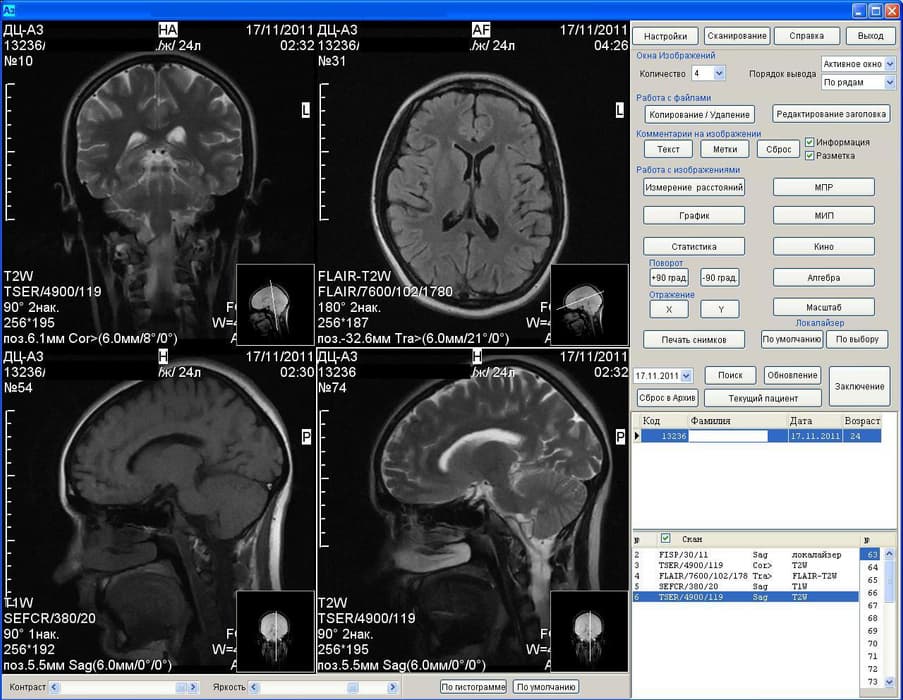

Результаты аппарата МРТ Аз-300

Отмечается, что ученые восстановили функциональные сети головного мозга здоровых людей и пациентов с депрессией. Методика, получившая название «консенсусный подход», выявила различия в результатах функциональной МРТ у двух групп людей.

Разработка российских ученых позволяет с высоким уровнем точности определить депрессию. В ближайшее время специалисты БФУ планируют создать систему автоматического распознавания депрессии с помощью МРТ.